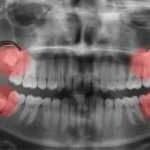

親知らずは4本同時に抜歯できる?注意点やメリット・デメリットを解説

こんにちは、武蔵小杉駅徒歩3分の歯医者、武蔵小杉ネゴ歯科矯正歯科です。 親知らず ...